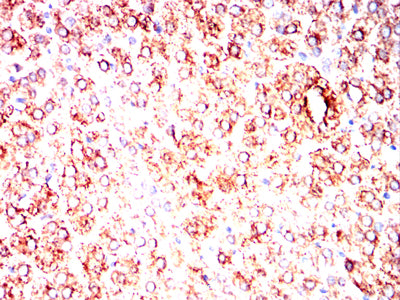

![MUC13 Mouse mAb[63965]](https://img1.dxycdn.com/p/s14/2025/0922/964/8005176193746699691.jpg)

Immunohistochemical analysis of paraffin-embedded human colon cancer tissues using MUC13 mouse mAb with DAB staining.